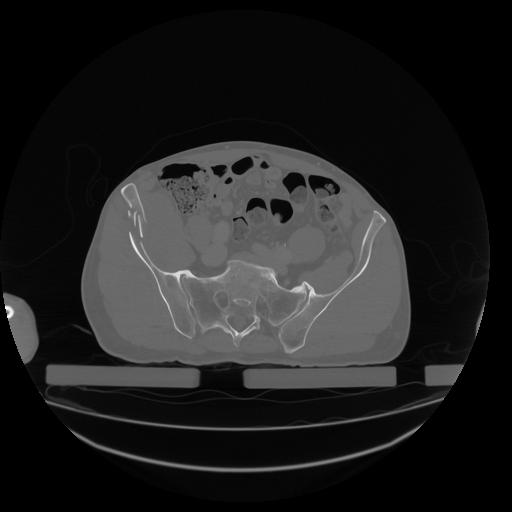

34 CUERPO,CE,Vol,1.0,CUERPO,,